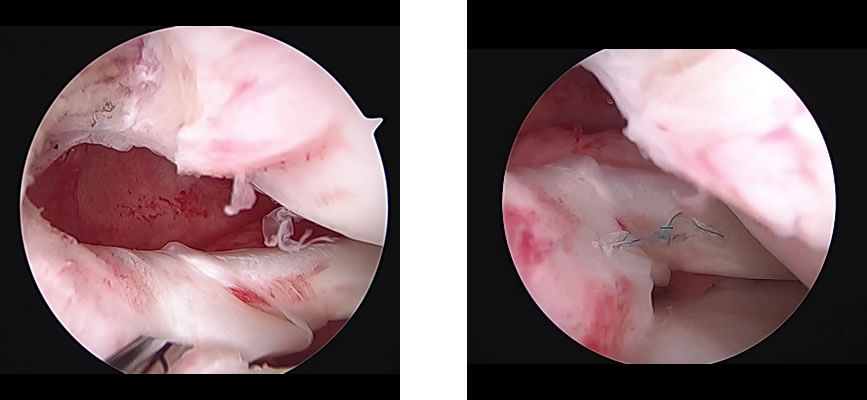

半月板縫合術・半月板切除術(半月板損傷)

関節鏡を用いて、縫合あるいは損傷部位の部分切除を行います。

半月板は膝関節の重要な役割を担っているため、可能な限り縫合を行っておりますが、縫合が困難な場合は切除部位を最小限にとどめられるように行います。